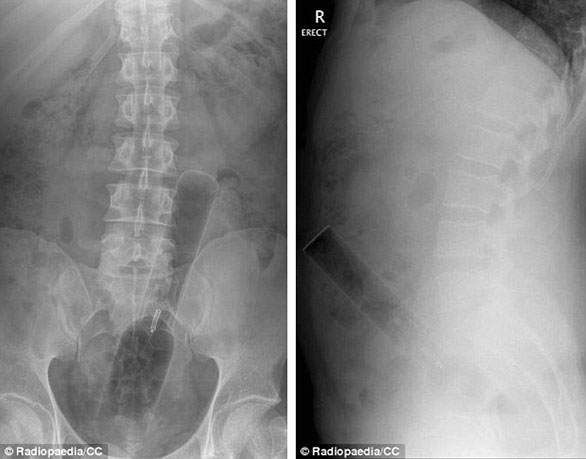

ضم الموقع مجموعة من الصور للأشعة السينية توضح أجساماً غريبة رُصدت داخل أجساد المرضى، ما أثارت دهشة الأطباء الذين قرروا رفعها على موقع طبي متخصص كمادة تعليمية ومرجعية بحثية واستشارية للدارسين في كليات الطب، والذي أنشئ من قبل طبيب أشعة أسترالي عام 2005، بحسب صحيفة دايلي ميل البريطانية.

صورة لأشعة "إكس راي" توضح دخول أنبوب لعلبة فيتامينات.